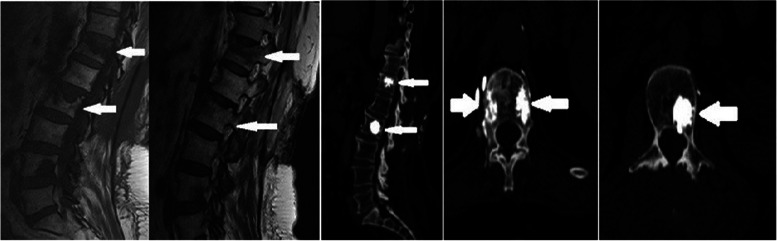

Fig. 2.

Sixty-four years old female patient. T12 and L2 vertebra metastatic involvement MRG images (preoperatively) and CT images after RFA and vertebroplasty

The reported rate of serious complications for percutaneous VP is low (< 10%); however, one study reported a PMM leakage rate of 81% visualised using CT [22]. Barragan-Campos reported 42 cases of PMM leakage cases from amongst 159 percutaneous VP procedures [23]; however, only 2 patients had serious complications. Furthermore, Nakatsuka reported that 4 patients developed hemiplegia and radiculopathy after RFA + VP, which was performed under CT fluoroscopy guidance [24]. In our study, PMM leakage occurred in 4 (25%) of 40 patients who underwent VP, but no serious complications were observed (Fig. 2).